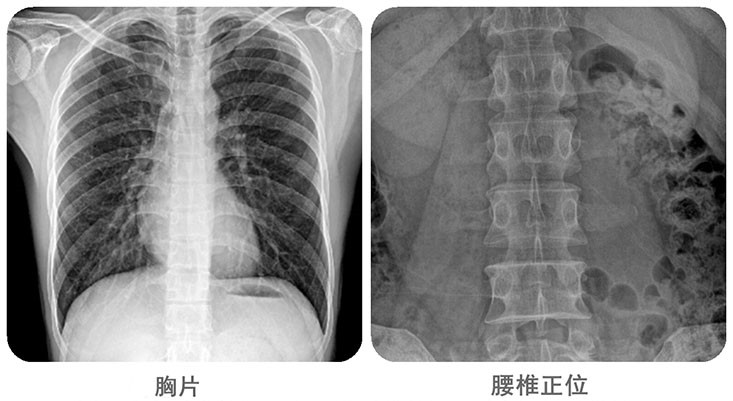

清晰影像,便于臨床診斷。移動(dòng)DR能夠滿(mǎn)足人體的頭部、四肢、胸腔、脊柱、腰椎、腹部等全身多部位的數(shù)字化攝影需求。